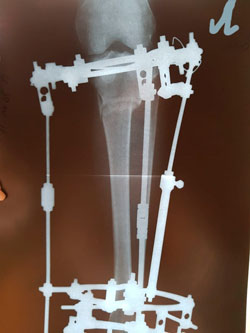

Исходник - 31 год.

Дата операции - 28.02.2019г.

Ротация с обеих сторон 30 градусов.

рентген в 65 дней.

рентген в 86 дней!

рентген в 86 дней.